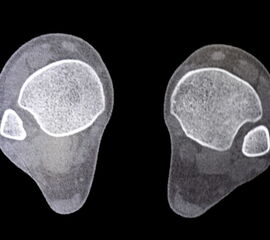

Die CT-Diagnostik erlaubt eine kritischere Beurteilung des DTFG. Die Wertigkeit zur Beurteilung von Syndesmosenverletzungen wurde in diversen Studien untersucht. Die Kongruenz im distalen Tibiofibulargelenk sollte in den axialen Schichten beurteilt werden 39. Aufgrund der hohen physiologischen Varianz, ist ein Seitenvergleich empfehlenswert (Abb. 5). So können die anteroposteriore Translation, Rotation und Verkürzung des betroffenen DTFG im Vergleich zum gesunden DTFG verglichen werden 40.